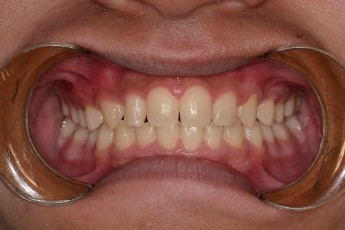

Before

After